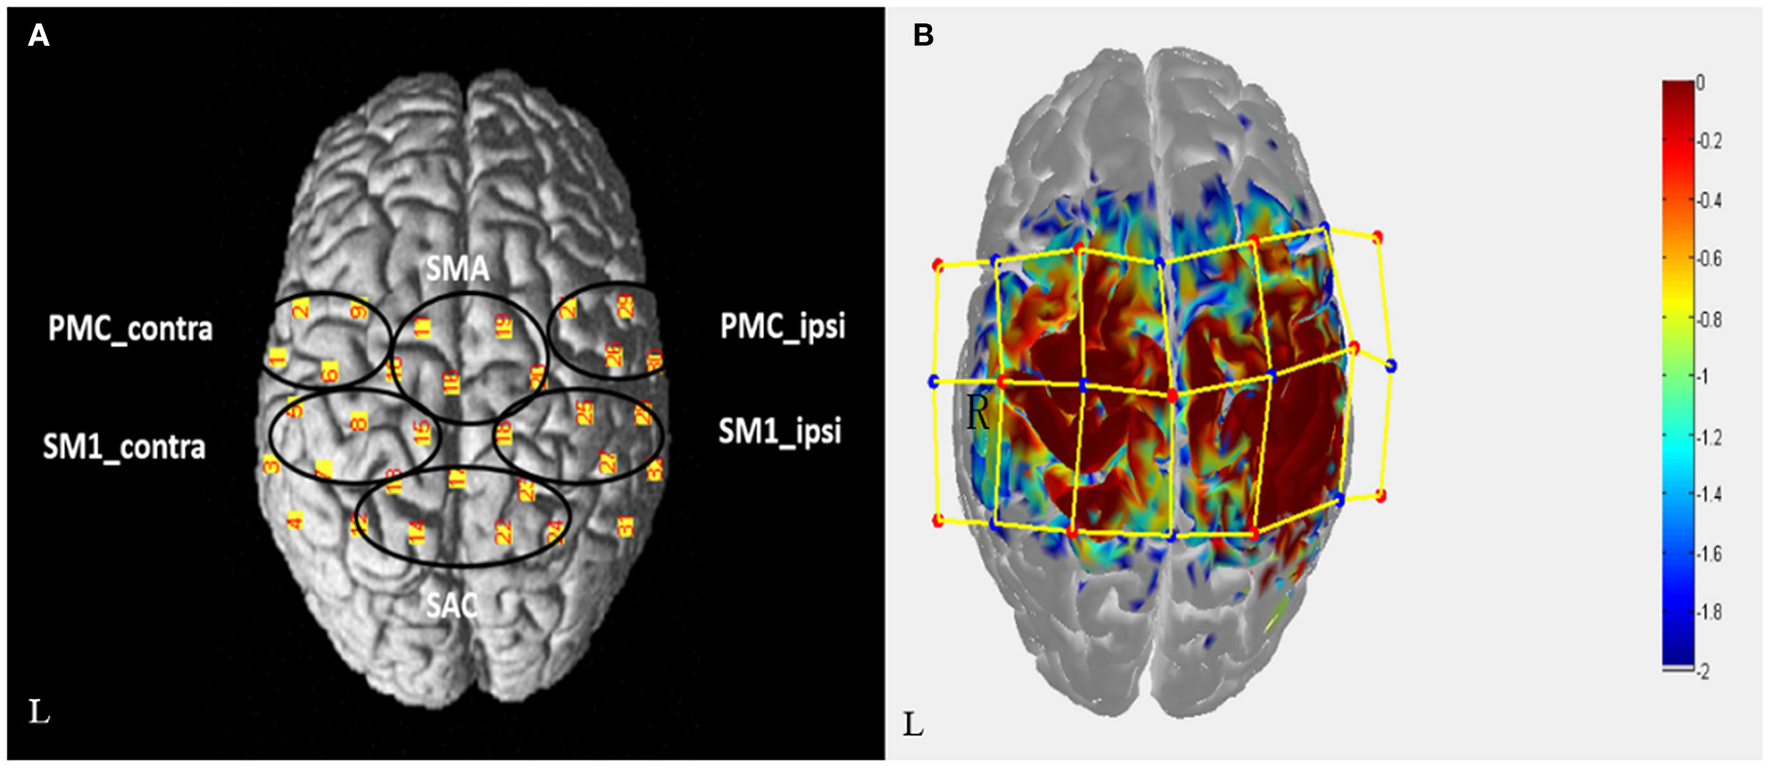

fNIRS equipment (Danyang Huicuang Medical equipment Co., Ltd., Jiangsu, China) will be used to record the hemodynamic data of patients before and after rehabilitation treatment. A total of 21 NIRS optrodes (11 light sources and 10 detectors, with wavelength of 730 and 850 nm, and sampling rate of 19 Hz) forming 32 observation channels. The optrodes will be fixed on the patient's head with a holder, covering the bilateral frontal and parietal regions. Resting-state session and task session will be included in fNIRS evaluation. During the resting-state evaluation, patients will be asked to sit and relax for 8 min, and the resting data will be collected. The task session involved repetitive movements of flexion and extension of the hemiplegic fingers at frequency of 1 Hz with verbal cues, using a block design [six cycles: rest (10 sec); hand movements (15 sec); rest (20 sec)]. A three-dimensional digitizer (Patriot, America) will be used to collect the 3D coordinate information of the optrodes and channels to ensure the accuracy of the observed brain area and to be consistent in multiple measurements. According to the Brodmann area (BA) and anatomical locations of cortex, the observation channels will be divided into six ROIs (regions of interest): ipsilesional premotor cortex, PMC_ipsi; contralesional premotor cortex, PMC_contra; ipsilesional primary sensorimotor cortex, SM1_ipsi; contralesional primary sensorimotor cortex, SM1_contra; supplementary motor area, SMA; Somatosensory Association Cortex, SAC (Figure 3).

Figure 3

(A) The arrangement map of fNIRS channels in the cortex, which is divided into 6 ROIs. (B) Light sources (red dot, 11) and detectors (blue dot, 10) forming 32 channels (yellow line). The sensitivity distribution map of photons in the cortex is simulated by Monte Carlo, and the redder the region is, the stronger the sensitivity is.